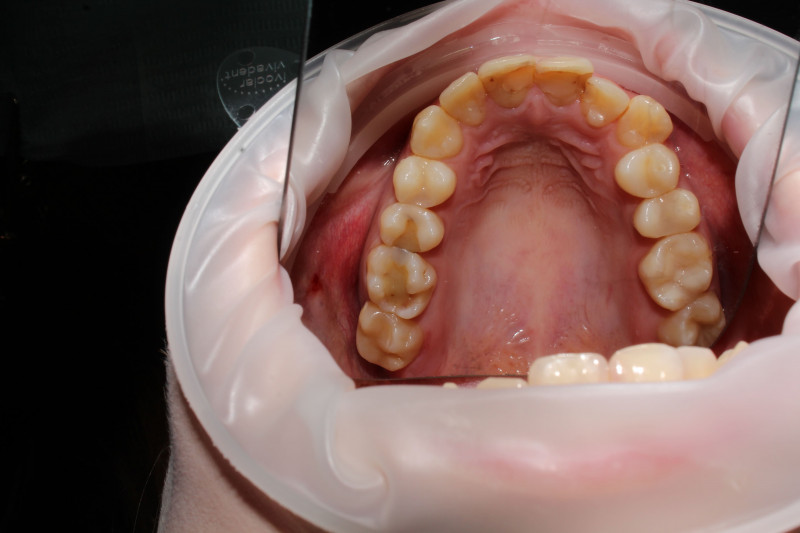

19 работ в портфолио

Щербакова (Полякова) Анна Сергеевна принимает в сети семейных стоматологических клиник ИЛАТАН в Москве. Стаж 11 лет. Специализируется на детской стоматологии и эндодонтическом лечении, по которым клиника оказывает 14 услуг. Имеет 19 работ до/после в портфолио. Квалификация специалиста подтверждена 21 лицензиями, сертификатами и наградами, а опыт 13 отзывами пациентов, из которых 13 положительные. Для уточнения дополнительной информации о специалисте или записи на прием можно позвонить по телефону